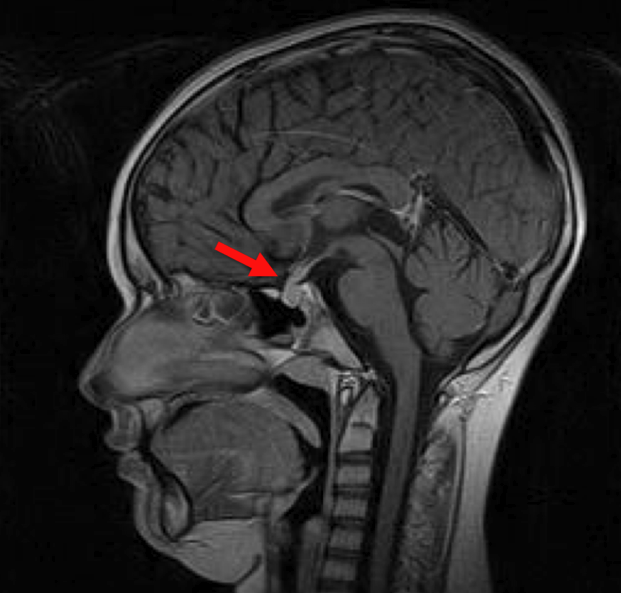

Vediamo F., 12 anni, per un rallentamento della crescita staturale, comparso da circa un anno. Ci viene detto inoltre che da 2 anni presenta polidipsia (beve 3-4 l d'acqua al giorno) con poliuria (4 l di urine/die). Alla visita appare in buone condizioni generali, obiettivit� nella norma, sviluppo prepubere (S1, PH1). Dagli esami di laboratorio si rileva ipernatriemia (Na 149 mEq/l) con osmolalit� plasmatica ai limiti superiori della norma (294 mOsm/kg) e bassa osmolalit� urinaria (174 mOsm/kg), con un rapporto tra le due pari a 0,59, indicativo di un difetto totale di ADH. Viene avviata terapia con desmopressina che porta a normalizzazione della diuresi e dei valori di laboratorio, confermando l'ipotesi di diabete insipido centrale. Dal punto di vista ormonale risultano nella norma prolattina, TSH, ACTH, cortisoluria nelle 24 ore, test GnRH (valori prepuberali) mentre il test da stimolo del GH con arginina mostra un deficit di secrezione (picco 1,6 ng/dl) con bassi livelli di IGF1. Nella norma emocromo, indici di flogosi, transaminasi, creatinina, glicemia, anti-tTG, visita oculistica e neurologica, campimetria. La RM encefalo mostra: "adenoipofisi aumentata di volume (9 mm di spessore) che tende a conglobare e a ispessire il peduncolo ipofisario. La struttura ghiandolare risulta omogenea anche dopo mdc con impregnazione che coinvolge anche il peduncolo. Non riconoscibile invece la neuroipofisi� (Figura 1).

Figura 1.